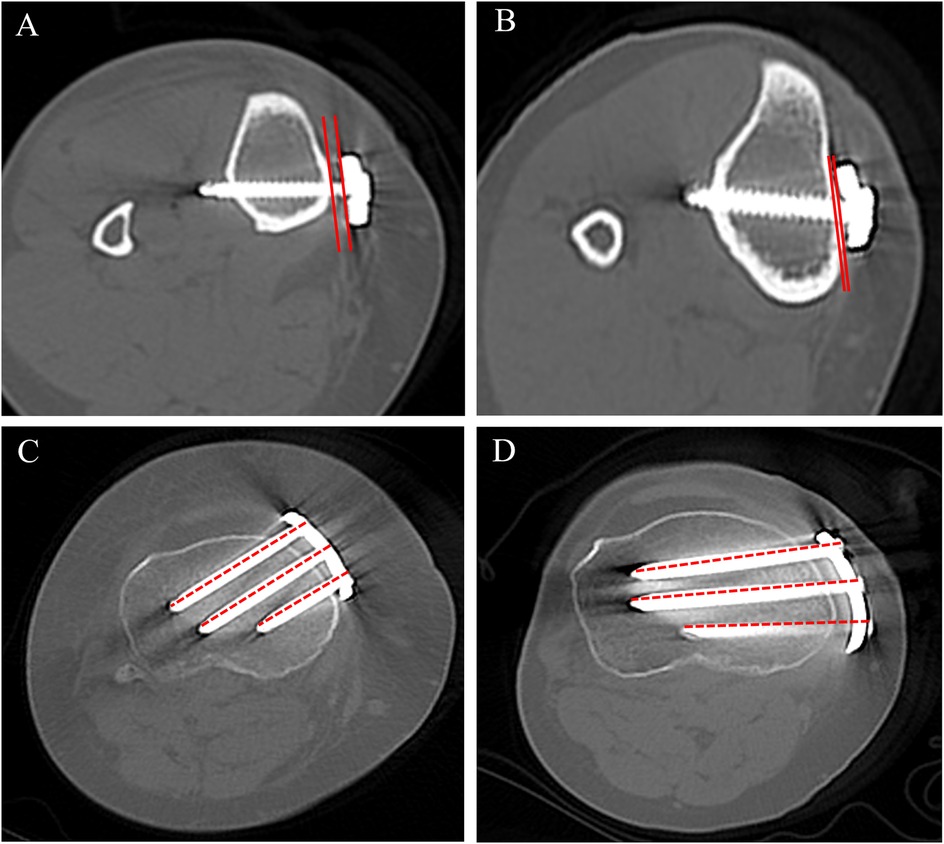

Background: High tibial osteotomy (HTO) corrects varus malalignment and unloads the medial knee compartment, yet the conventional T-shaped locking plate may cause discomfort due to suboptimal anatomic conformity. We developed a novel locking plate to improve anatomic fit and fixation stability and compared it with the T-shaped plate in Anterior Popliteus Transtibial-tuberosity high tibial osteotomy (APTT-HTO). Methods: This single-center retrospective observational comparative study included 14 consecutive patients who underwent APTT-HTO between August 2024 and June 2025. Patients were grouped by implant type (novel plate: n = 7; T-shaped plate: n = 7). Postoperative CT quantified plate orientation/position, plate–bone conformity (gap and position mismatch), screw alignment, and standard alignment parameters (hip–knee– ankle angle [HKA], posterior tibial slope [PTS]). Results: The novel plate showed more posteromedial placement and superior anatomic conformity. The plate angle relative to the posterior tibial condylar reference line was larger with the novel plate (74.49° ± 8.76°) than with the T-shaped plate (62.62° ± 7.05°, P<0.05). The proximal central screw–plate angle was smaller (5.70° ± 4.80° vs 27.48° ± 6.05°, P<0.05), the plate–bone gap was reduced (1.84 ± 0.68 mm vs 2.98 ± 0.38 mm, P<0.05), and plate position mismatch was lower (20.20% ± 7.70% vs 37.70% ± 10.00%, P<0.05). Proximal and distal offsets considered separately were not significantly different (P>0.05). Both groups achieved the planned coronal correction, and sagittal PTS remained stable (P>0.05). Conclusions: In this CT-based cohort, the novel anatomically contoured locking plate achieved superior anatomic conformity in APTT-HTO—characterized by more posteromedial positioning, a more favorable screw trajectory, and improved plate–bone apposition—compared with a conventional T-shaped plate. These findings warrant confirmation in larger, prospective studies.